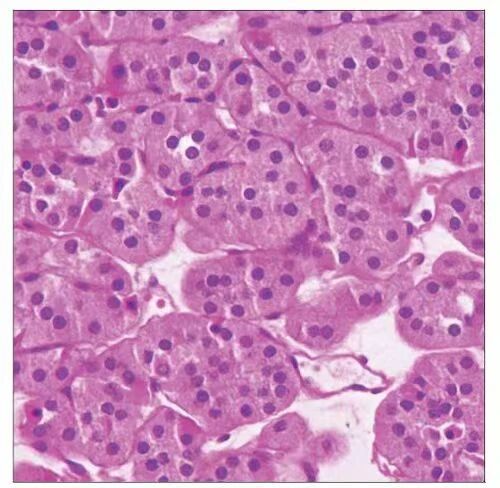

K 的病理活检结果出来了,那一大坨肿瘤组织的性质是:肾嗜酸细胞瘤。

我和同事不可置信地对视了一眼:什么?嗜酸细胞瘤?真的没有搞错吗?肾嗜酸细胞瘤,大家公认的良性肿瘤,扩散了?

肾嗜酸细胞瘤组织切片(非本病例)

图源:参考资料 [2]

肾嗜酸细胞瘤占肾实质肿瘤的 3~7%,男性患者约为女性患者的 2 倍,患病年龄与肾透明细胞癌相似,高发年龄在 70 岁左右。病理上该细胞由细胞质丰富、且呈嗜酸性的大细胞构成,生长缓慢,极少出现远处转移,预后良好。

临床诊断主要依靠影像学检查,确诊需依靠手术后病理检查,肿瘤组织穿刺活检病理检查时易与肾透明细胞癌、肾嫌色细胞癌、肾乳头状腺癌混淆。该病的细胞遗传学特点较明显,有 1 号染色体和 Y 染色体的缺失,14 号染色体杂合性缺失,11q13 重排等。